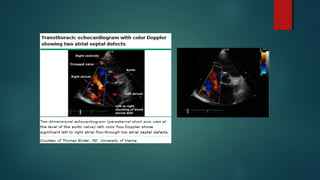

ECOCARDIOGRAMA

 Debe solicitarse siempre ante sospecha de HP.

 Utilidad:

 Estimación de la Presión de la Arteria Pulmonar.

 Tamaño del VD.

 Tamaño de la AD.

 Función Sistólica y Diastólica.

 Función Valvular (principalmente insuficiencia tricuspidea)

 Shunt Intracardiacos.

ECOCARDIOGRAMA  Debe solicitarsesiempre ante sospecha de HP.  Utilidad:  Estimación de la Presión de la Arteria Pulmonar.  Tamaño del VD.  Tamaño de la AD.  Función Sistólica y Diastólica.  Función Valvular (principalmente insuficiencia tricuspidea)  Shunt Intracardiacos. Lewis J Rubin, MD et al. «Clinical features and diagnosis of pulmonary hypertension in adults”. UPTODATE. Literature review current through: May 2015.